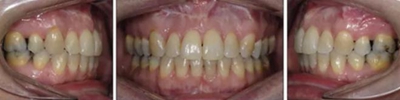

患者曾行正畸治療,現覺笑容不美觀前來就診?;颊哒嬗^及側貌示下頜發(fā)育不足,偏高角,唇閉合不全。上下頜中線齊。覆合、覆蓋4毫米。磨牙關系及尖牙關系II類。上頜擁擠度4mm,下頜擁擠度6mm。4顆第一前磨牙在第一次正畸治療時已拔除。上下牙弓呈尖圓型,牙弓狹窄。

治療結果:

患者側貌改善,下唇唇肌緊張消失,上下唇可自然閉合。磨牙及尖牙關系糾正至I類,覆合覆蓋正常。上下頜弓型糾正至卵圓形,牙弓寬度增加。頭影測量分析示SNA角81.8°,ANB角3°。頭影測量重疊圖示下頜骨向后旋轉,垂直面高度略有增加。